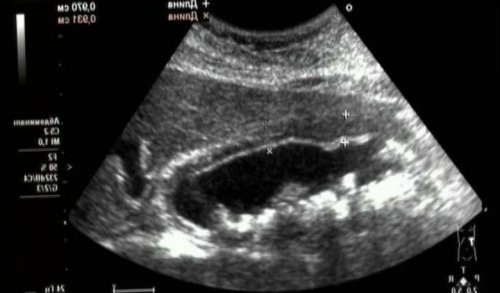

• УЗИ брюшной полости. Ультразвуковое исследование позволяет их формирования никуда